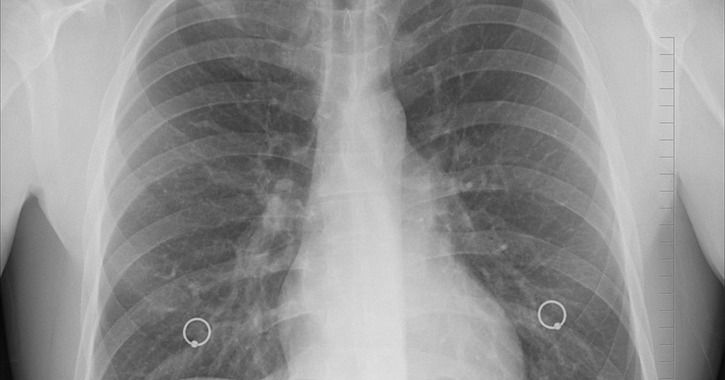

Comprising more than 100,000 chest X-ray images, the collection could improve artificial intelligence, diagnoses, and global heath, Ronald M. Summers, who led the effort, told Healthcare Analytics News™. The project came out of a radiology department at the National Institutes of Health’ Clinical Center, where Summers works as a senior investigator in an imaging and computer-aided diagnosis lab.

They compiled the X-ray images from more than 30,000 patients, including many with advanced lung disease, at the NIH Clinical Center. Then Summers used natural language processing to extract information from corresponding radiology reports, he said.